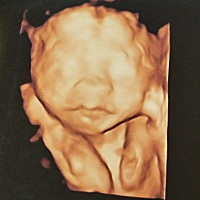

末次24号,这是有了吗